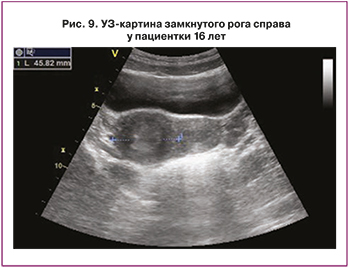

По данным УЗИ органов малого таза (рис. 9) матка отклонена влево, положение anteflexio, контуры ровные, четкие. Размеры матки: тело 46×29×32 мм, шейка 22×22 мм. Шеечно-маточный угол выражен. Эхо-структура миометрия не изменена. Эндометрий 10,8 мм, однородный. Яичники расположены в углах матки. Правый 38×20×33 мм, V=12,94 см3. Эхо-структура не изменена, содержит фолликулы 7–8 мм, а также кистозную структуру округлой формы 19×15 мм с однородным мелкодисперсным изоэхогенным аваскулярным содержимым. Левый 38×25×33 мм, V=15,88 см3. Эхо-структура не изменена, содержит фолликулы 5–7 мм, 6–8 в срезе. К правому ребру матки интимно прилежит образование овальной формы размерами 47×31×35 мм, с неравномерно утолщенной до 6,5–14 мм, гипоэхогенной стенкой и полостью до 22×18 мм в диаметре, с несколько неоднородным по структуре содержимым за счет более эхогенного слоя у стенок. Свободная жидкость выявлена в умеренном количестве справа и позади матки. Заключение по данным УЗИ: состояние после удаления замкнутого рога справа (в анамнезе). Эхо-признаки очаговой формы аденомиоза правой стенки матки или нерадикально резецированного правого маточного рога. Окончательный клинический диагноз: Порок развития мочеполовых органов. Двурогая матка с замкнутым функционирующим маточным рогом справа, спаечный процесс в малом тазу, пациентке рекомендовано оперативное вмешательство.